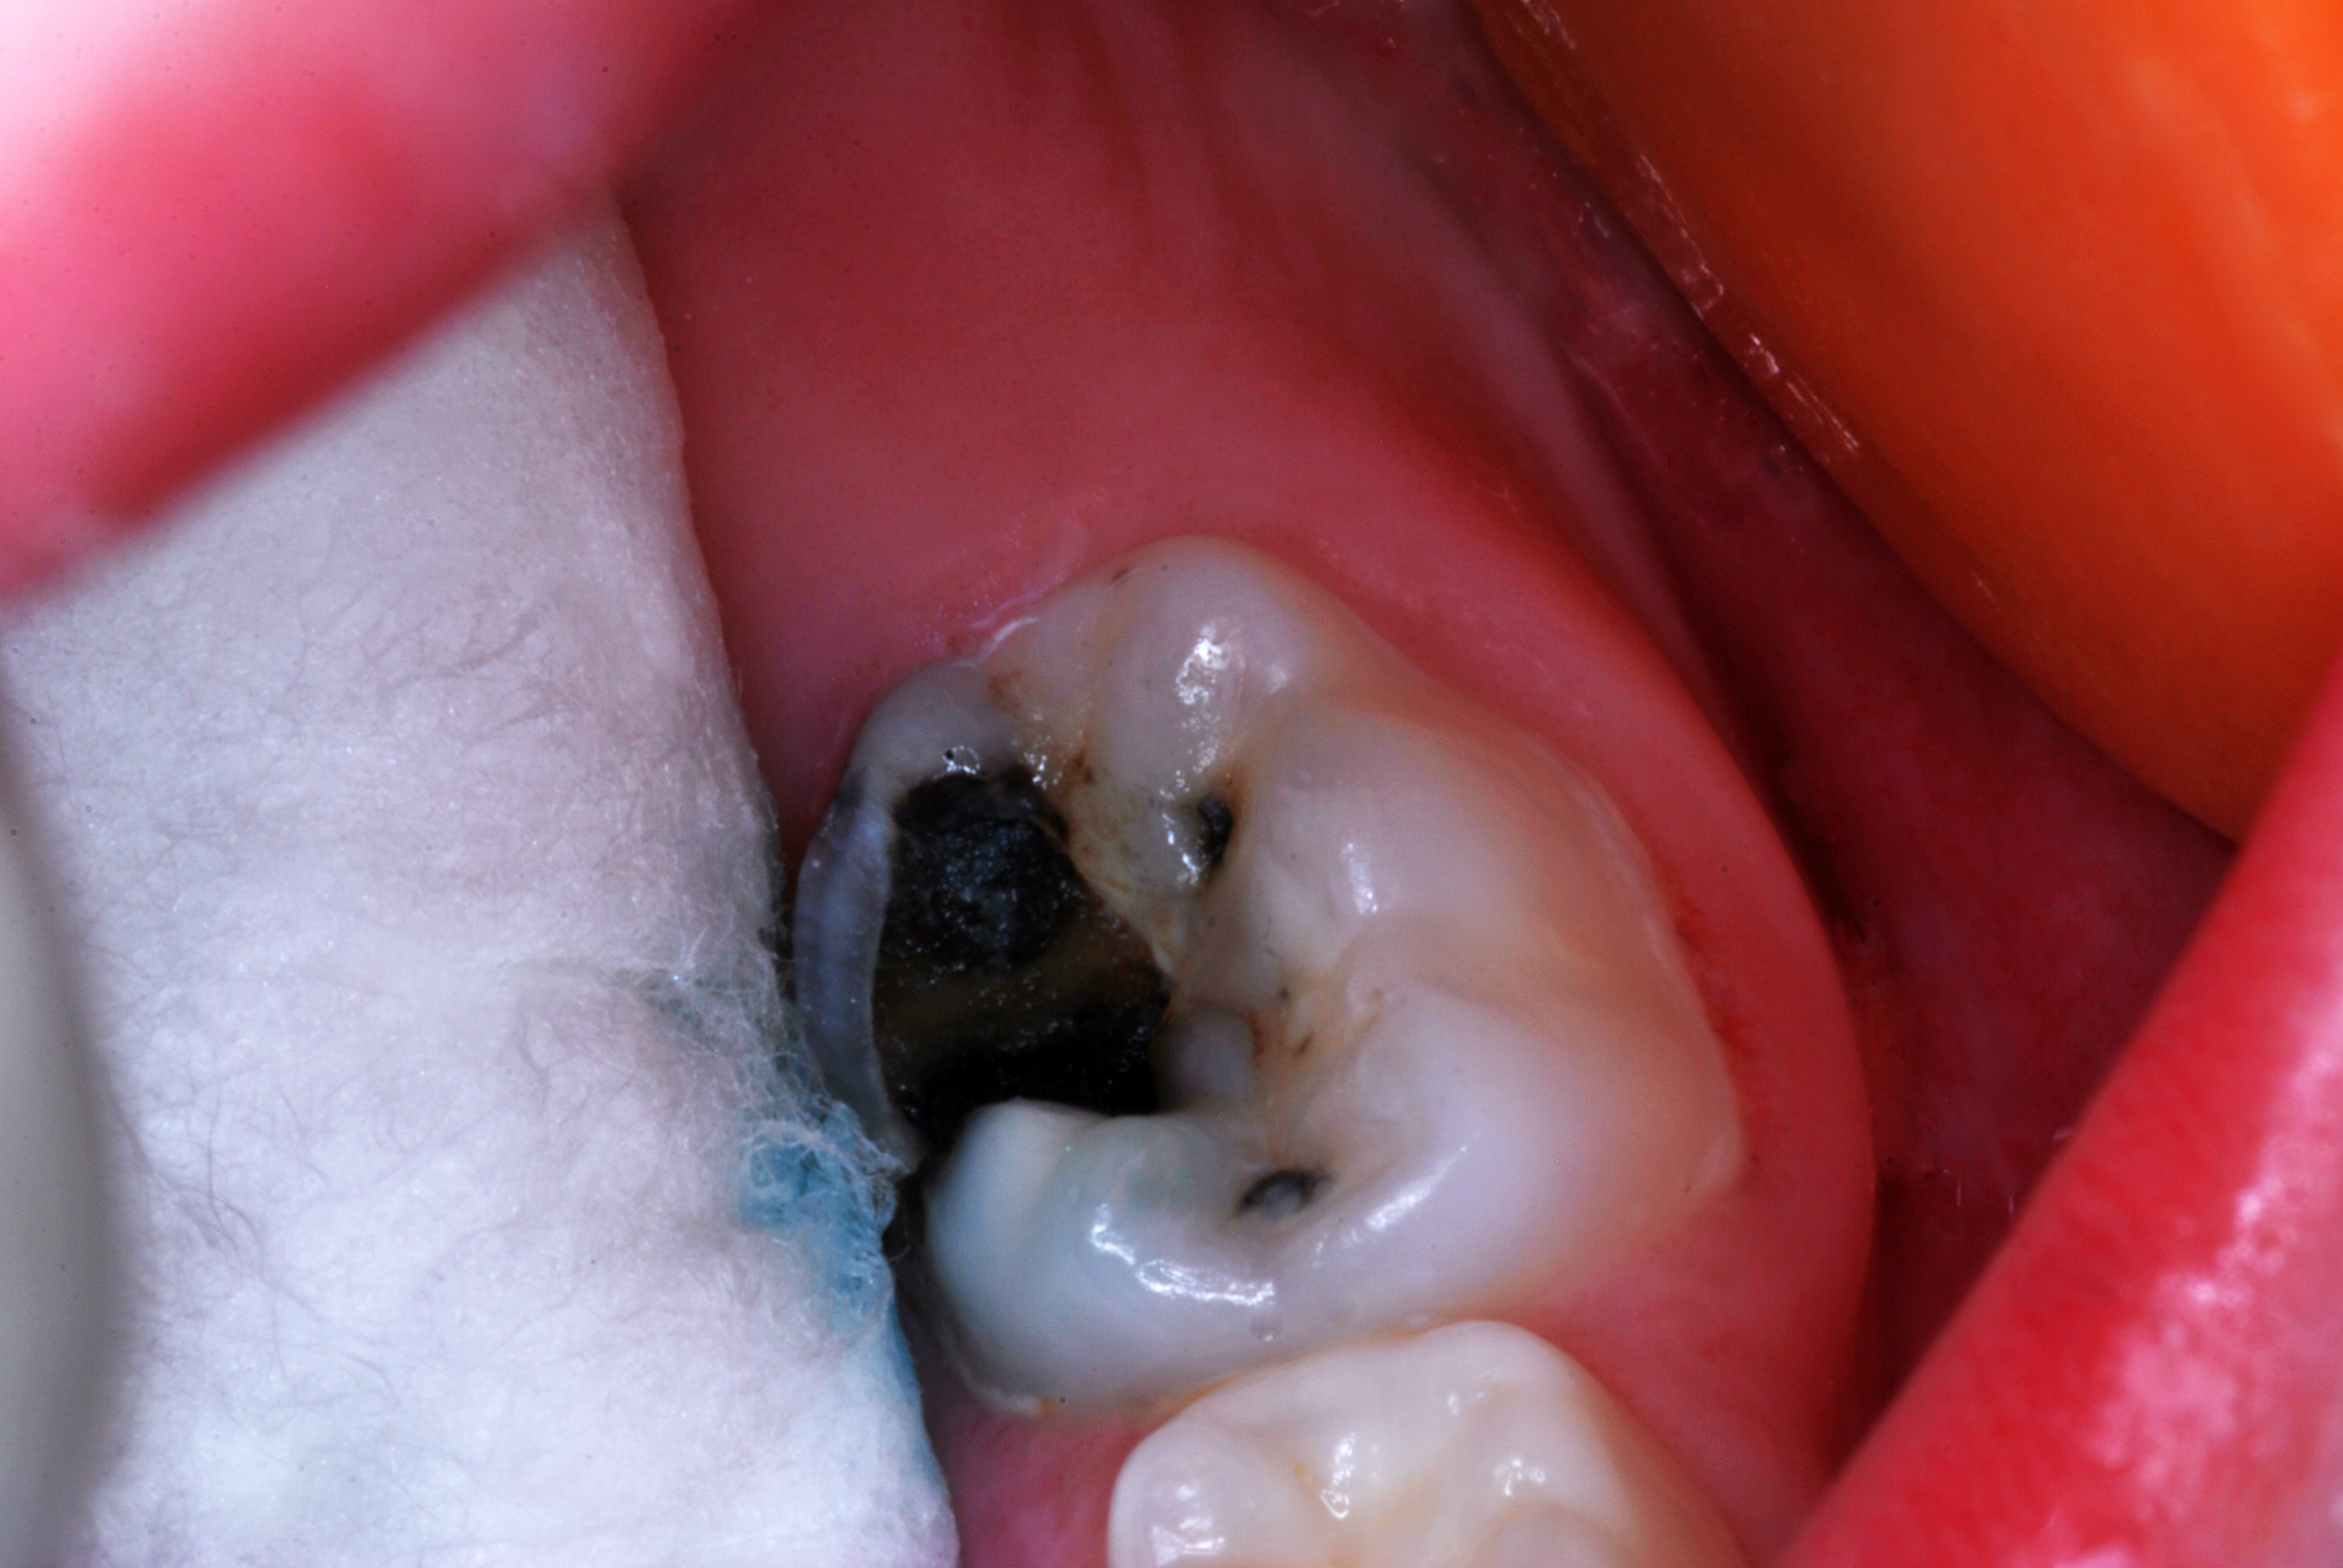

SDF was developed in Osaka, Japan, in 1969.24,25 During the next 5 decades, its use and related research spread around the world.26-32 Various formulations of SDF (Bioride®, Densply Industria e Comericio Ltda; e-SDF, Kids-e-Dental Llp; Riva Star, SDI; Saforide®, Toyo Seiyaku Kasei Ltd) have been developed in different countries to attenuate dental caries infections. In 2014, an SDF solution made up of 62% water, 25% silver, 8% ammonia, and 5% fluoride (Advantage Arrest® Silver Diamine Fluoride 38%, Elevate Oral Care, LLC) was the first to gain approval by the US Food and Drug Administration to be used in the United States as a tooth desensitizing agent33; however, others have since been cleared as well. Its ability to affect dental caries pathodynamics has developed into an exceedingly popular off-label use by dentist clinicians. Figure 1 depicts an example of a malformed and carious permanent first molar that had been treated with SDF followed by 2.5% sodium fluoride varnish 6 months and 12 months prior when it was only partially erupted. This strategy attenuated the caries infection for over a year, until the patient, an extremely anxious 7-year-old boy, was able to tolerate routine restorative treatment.

(1.) Hypocalcified/carious first molar, 12 months after SDF application.

Figure 1